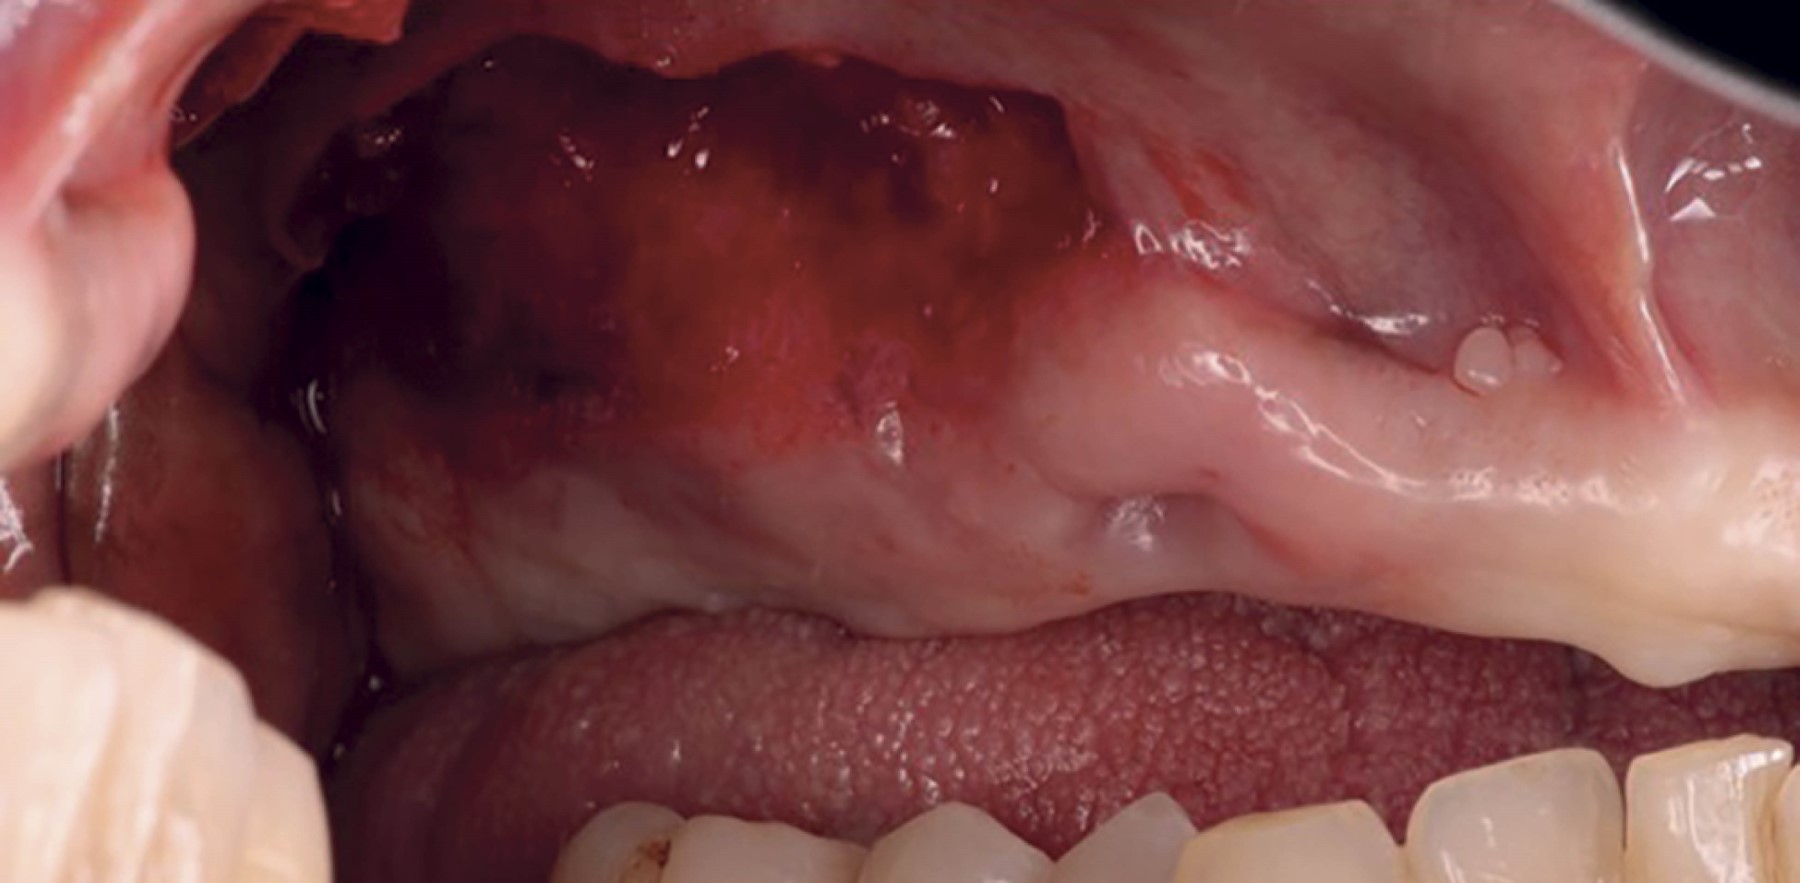

En la revisión postquirúrgica a las seis semanas, se observaron mediciones de 9 mm desde el borde coronal de la encía insertada hacia la línea mucogingival en comparación con la situación inicial (Figuras 6, 7 y 8).

Figura 6

Figura 7

Figura 8